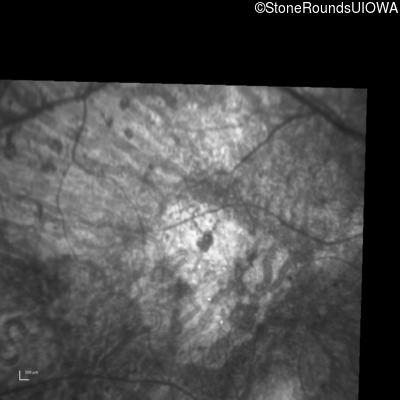

Infrared Fundus Photograph - Left - Hand Motion 6" sc

Exemplar